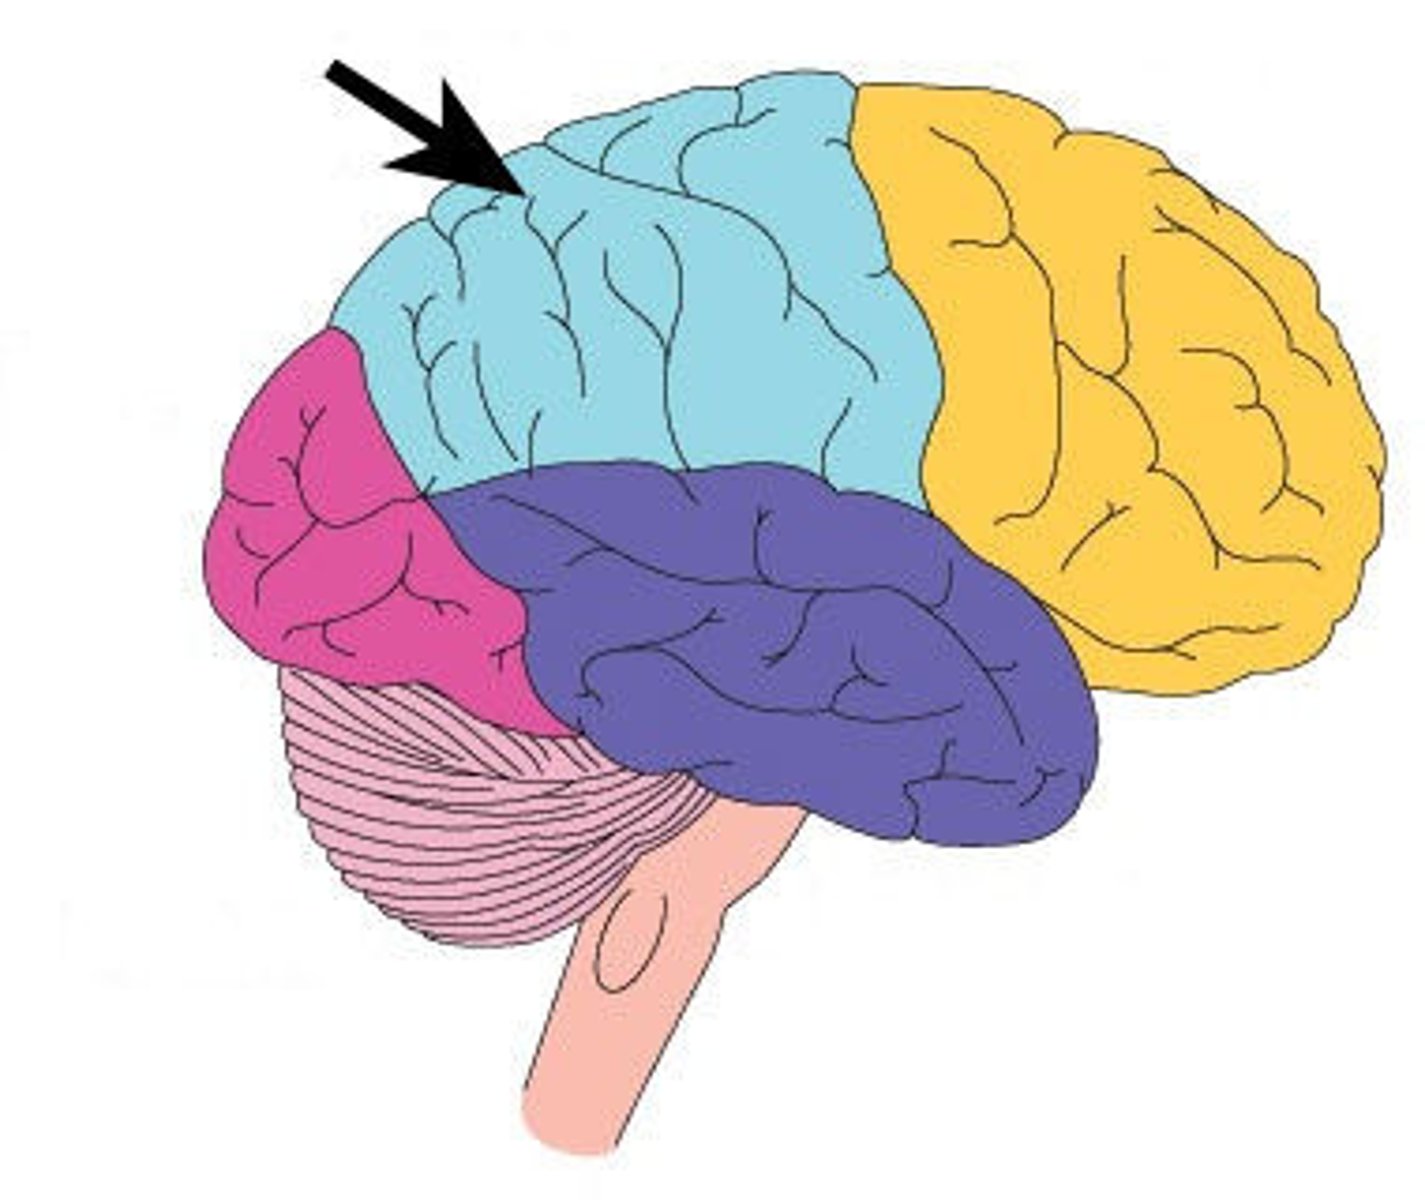

Cerebrum: Sulci and Gyri

Central Sulcus,

Precentral gyrus,

Postcentral gyrus

Central Sulcus

Precentral Gyrus

Postcentral Gyrus

Surface lobes of the cerebrum

Frontal Lobe,

Temporal Lobe,

Parietal Lobe,

Occipital Lobe